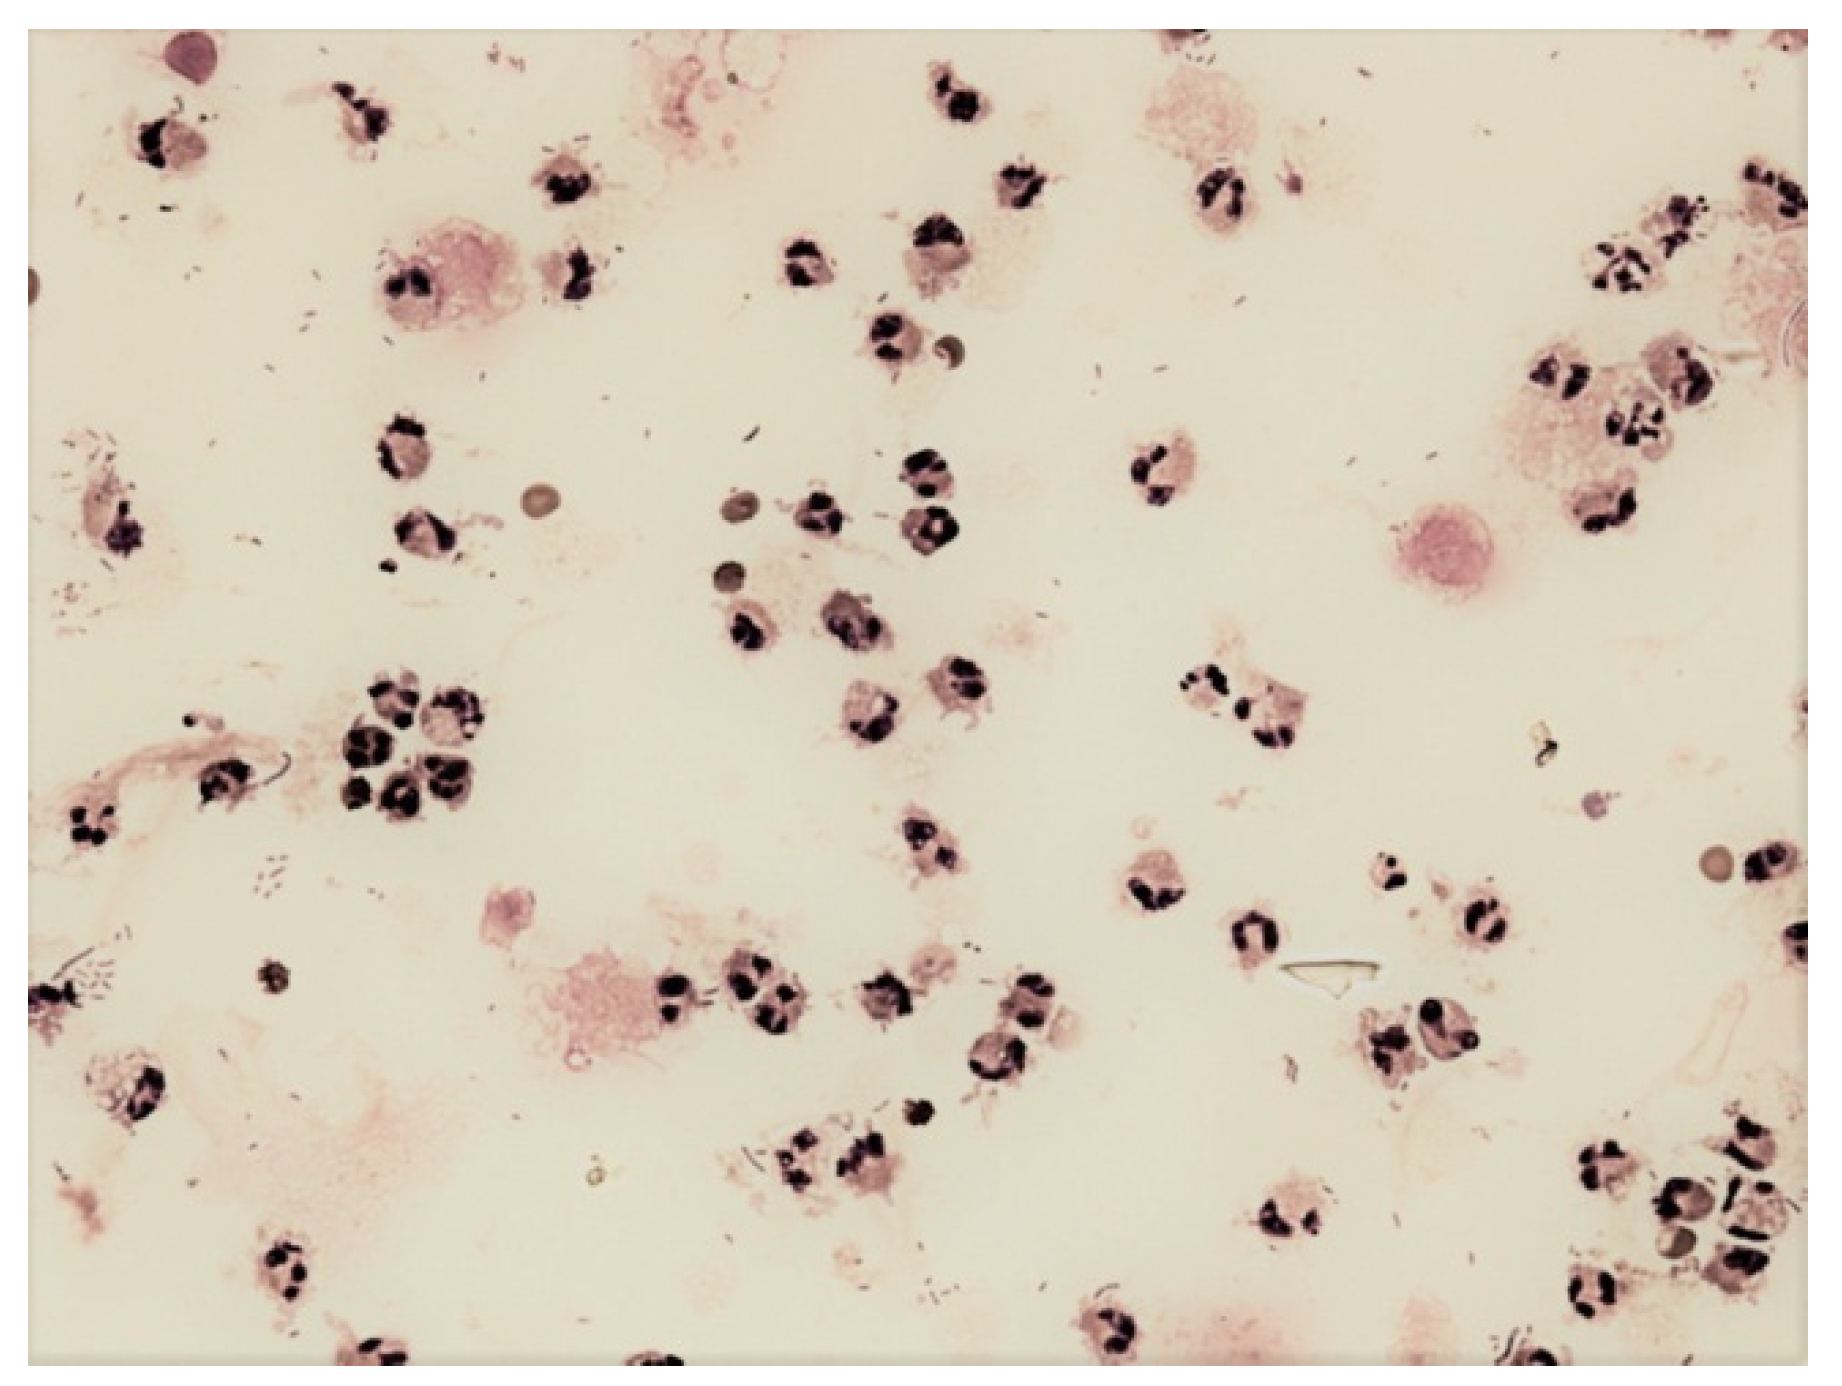

Figure 7.

Predominance of neutrophils and bacteria in the cerebrospinal fluid; KEB = −4743.5; purulent inflammation in the CNS induced by infection Streptococcus pneumoniae.